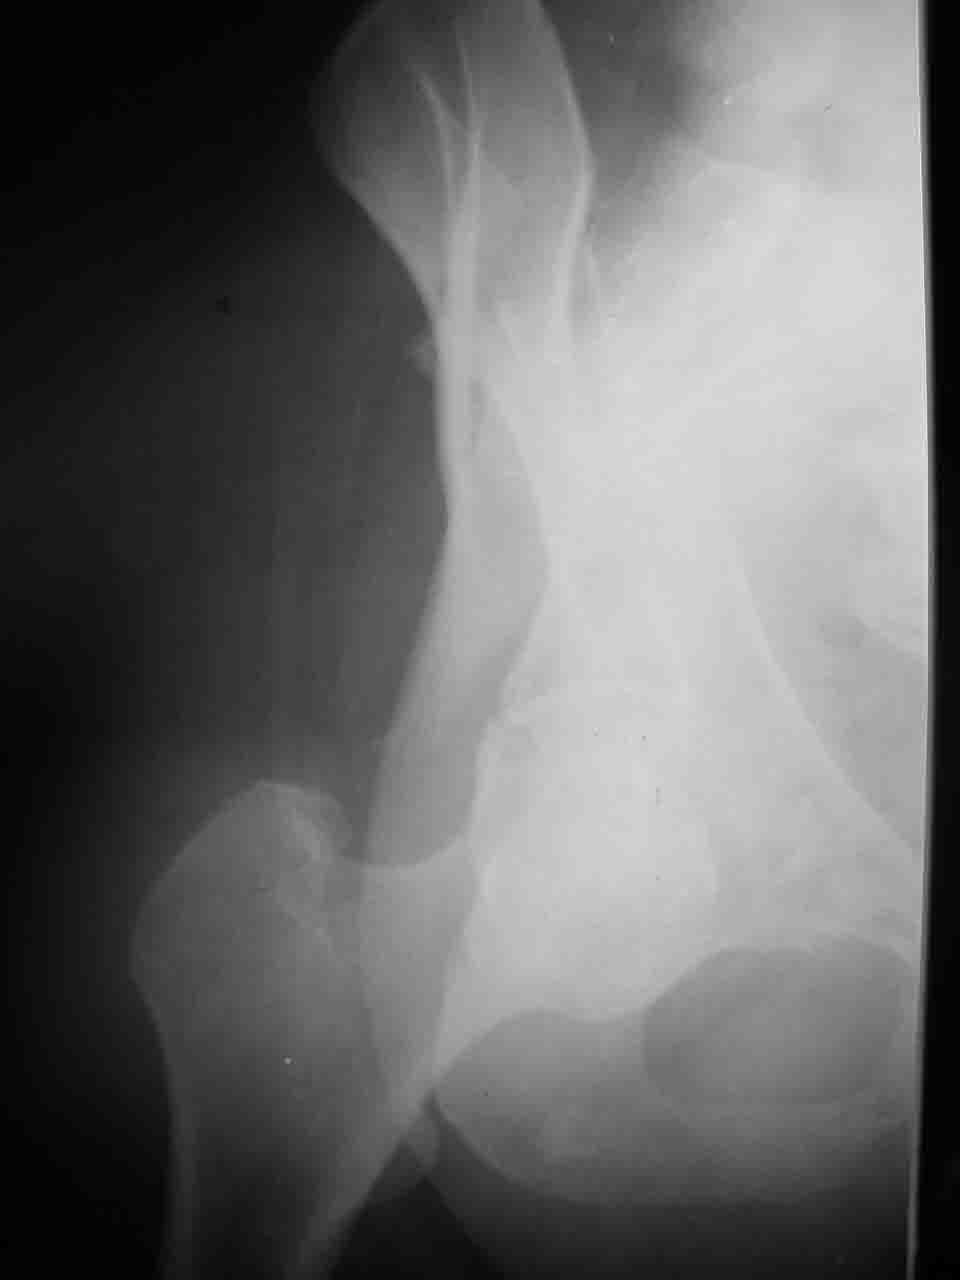

Уважаемые коллеги,43 летний мужчина, попав в автоаварию 13.10.2004, получил оскольчатый перелом обеих колонн левой вертлужной впадины.

На рентгенограммах - высокий двухколонный перелом вертлужной впадины с нарушением конгруэнтности, имеется обратная клиновидность суставной щели.

Спасибо за комментарии и рекомендации. Откровенно говоря, больного я прооперировал на прошлой неделе, через 5 дней после аварии и проблем с ним пока никаких нет, на удивление при достаточно обширной диссекции (илиофеморальный доступ) болей практически нет, так что больной самостоятельно садится в кровати, выполняет активные движения в оперированном суставе, сгибая до 60 градусов пока, далее с ассистенцией.

Причиной обращения к сообществу были возникшие непосредственно после операции сомнения и разочарования полученным качеством репозиции: а надо ли было трогать перелом вообще, репозиция передней колонны технически была очень сложна для меня, хотя реконструкции была в той же последовательности, что Д-р А.В.Рунков рекомендовал, в какой-то момент безуспешных манипуляций стал думать о *вторичной конгруэнтности*, которую не так давно обсуждали на

форуме и скелетном вытяжении. С репозицией и фиксацией задней колонны и отдельно задне-верхней стенки впадины проблем не возникло. Послеоп. Рг граммы в приложении. Если возникнут какие-либо дополнения или поправки - был бы признателен.